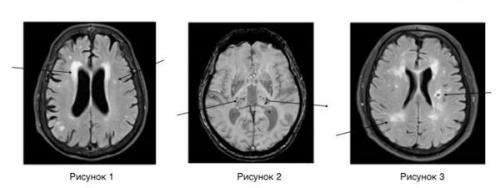

Верхние доли полушарий головного мозга являются одним из самых важных участков нашего мозга. Они отвечают за множество функций, таких как обработка информации, память, внимание, речь и многое другое. Но что, если эти доли полушарий головного мозга не работают должным образом? В этой статье мы рассмотрим некоторые заболевания, которые могут быть связаны с верхними долями полушарий головного мозга.

Вы видите, что верхние доли полушарий головного мозга играют очень важную роль в нашем организме. Если эти доли полушарий головного мозга не работают должным образом, это может привести к множеству заболеваний, таких как акромегалия, синдром Вильсона-Коновалова и синдром Аспергера. Поэтому важно обращать внимание на любые изменения в наших мозговых функциях и обращаться к врачу, если вы замечаете какие-либо проблемы.